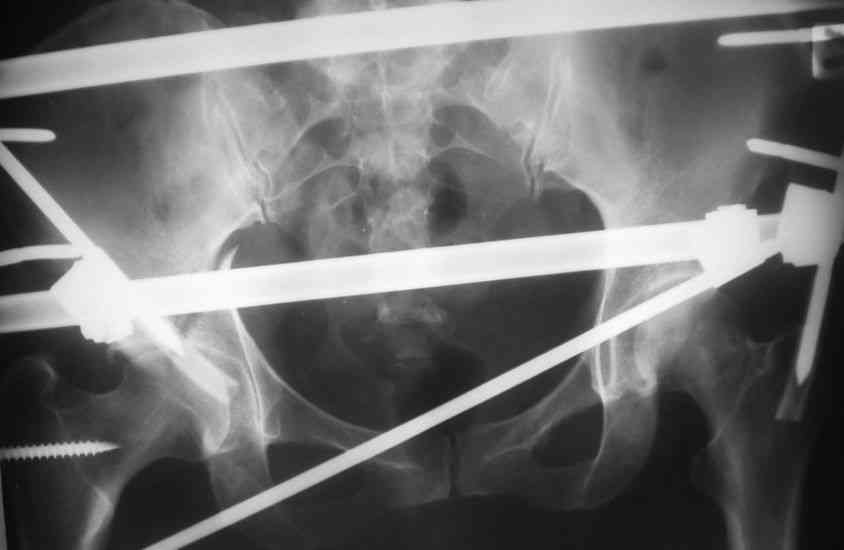

Пациентка 38 лет. В результате ДТП 02.09.06 получила поперечный перелом правой вертлужной впадины, центральный вывих правого бедра, разрыв правого крестцово-подвздошного сустава.

В одной из районных больниц вывих устранен, наложена система вытяжения по оси бедра и за вертельную область. Спустя 2 недели выполнен ВЧКО модулем "таз-бедро". Учитывая возраст пациентки и остаточный диастаз в области свода вертлужной впадины предполагается демонтаж аппарата, открытая репозиция и внутренний МОС вертлужной впадины через внутритазовый доступ.

На показанных снимках повреждение правого КПС не очень заметно...

У меня создалось впечатление( одна из РГ), что участок суставной поверхности нагрузочной зоны вертлужной впадины вдавлен( постарайтесь сделать КТ). Если это подтвердиться, то из внутритазового доступа отрепонировать будет невозможно.